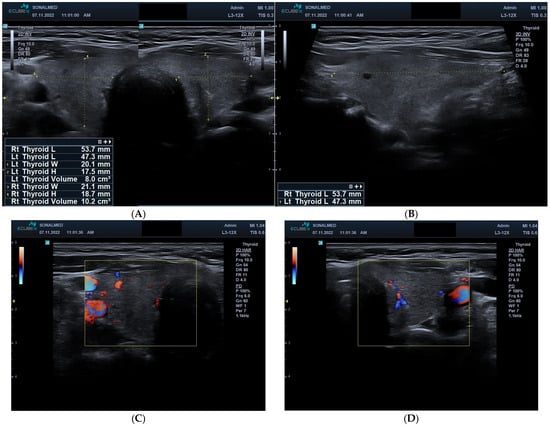

Progressive Destructive Hypothyroidism Associated with Sunitinib Therapy: A Three-Year Case Analysis

Sunitinib, a tyrosine kinase inhibitor (TKI) targeting vascular endothelial growth factor receptors (VEGFRs) and platelet-derived growth factor receptors (PDGFRs), is widely used in renal cell carcinoma. A broad spectrum of thyroid dysfunctions has been observed during TKI therapy, yet their mechanisms and clinical progression remain only partially explained. A longitudinal case analysis of a woman with metastatic clear-cell renal cell carcinoma treated with cyclical sunitinib therapy (4 weeks on, 2 weeks off) was performed. Thyroid function tests, clinical symptoms, and ultrasound imaging findings were evaluated over time and compared with treatment exposure and dose adjustments. Baseline thyroid function was normal. During the third cycle, thyroid-stimulating hormone (TSH) increased markedly (33.44–41.26 mIU/L), with free thyroid hormones initially remaining within reference limits. TSH fluctuations corresponded to treatment intervals before stabilising into persistent hypothyroidism requiring levothyroxine replacement. Thyroid ultrasound revealed progressive parenchymal destruction and a reduction in gland volume from 18 mL to approximately 2 mL over three years. Endocrine management enabled maintenance of biochemical euthyroidism, and systemic oncological treatment continued without interruption. Sunitinib treatment may lead to progressive destructive hypothyroidism. Routine surveillance of thyroid function is essential, and timely levothyroxine therapy facilitates continued anticancer treatment and symptom control. Full article

Show Figures

Figure 1